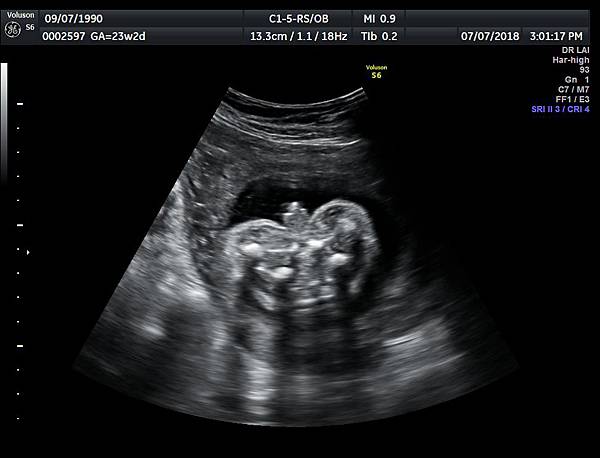

今天下午一位28歲第一胎的孕婦來診所做超音波檢查,之前他們一直認為懷的是女兒(檢查前資料顯示胎兒是女生);今天我的診斷胎兒是男生,但是懷疑有尿道下裂的問題(附圖 1~4),我的建議是抽羊水做染色體基因檢查,除了確定性別之外,也可以排除是否合併基因異常。

能在產前被診斷尿道下裂的個案大部分是嚴重型的penoscrotal type,需要比較複雜的手術,輕微型的尿道下裂絕大多數無法產前診斷。

診斷尿道下裂常用的鬱金香sign(tulip sign)(附圖 10.11.),它的特徵就是龜頭陷入陰囊中間,胎兒如果是男生,一定要看到龜頭離開陰囊,這樣就沒有問題,每次遇到尿道下裂的個案時,我都會有一個感觸,男生如果能站著尿尿都要很感恩。